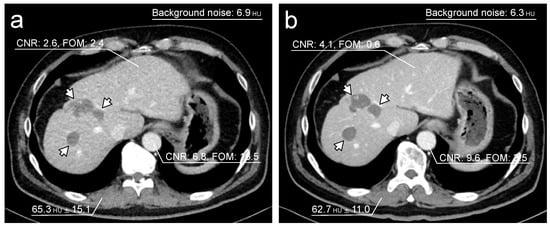

| CNR of liver | 2.76 (1.38–4.03) | 2.13 (1.42–2.73) | <0.0001 |

| FOM of liver (mSv−1) | 0.36 (0.09–0.93) | 2.24 (0.89–4.07) | <0.0001 |

| Background noise | 6.04 (5.45–6.93) | 8.36 (7.61–8.86) | <0.0001 |